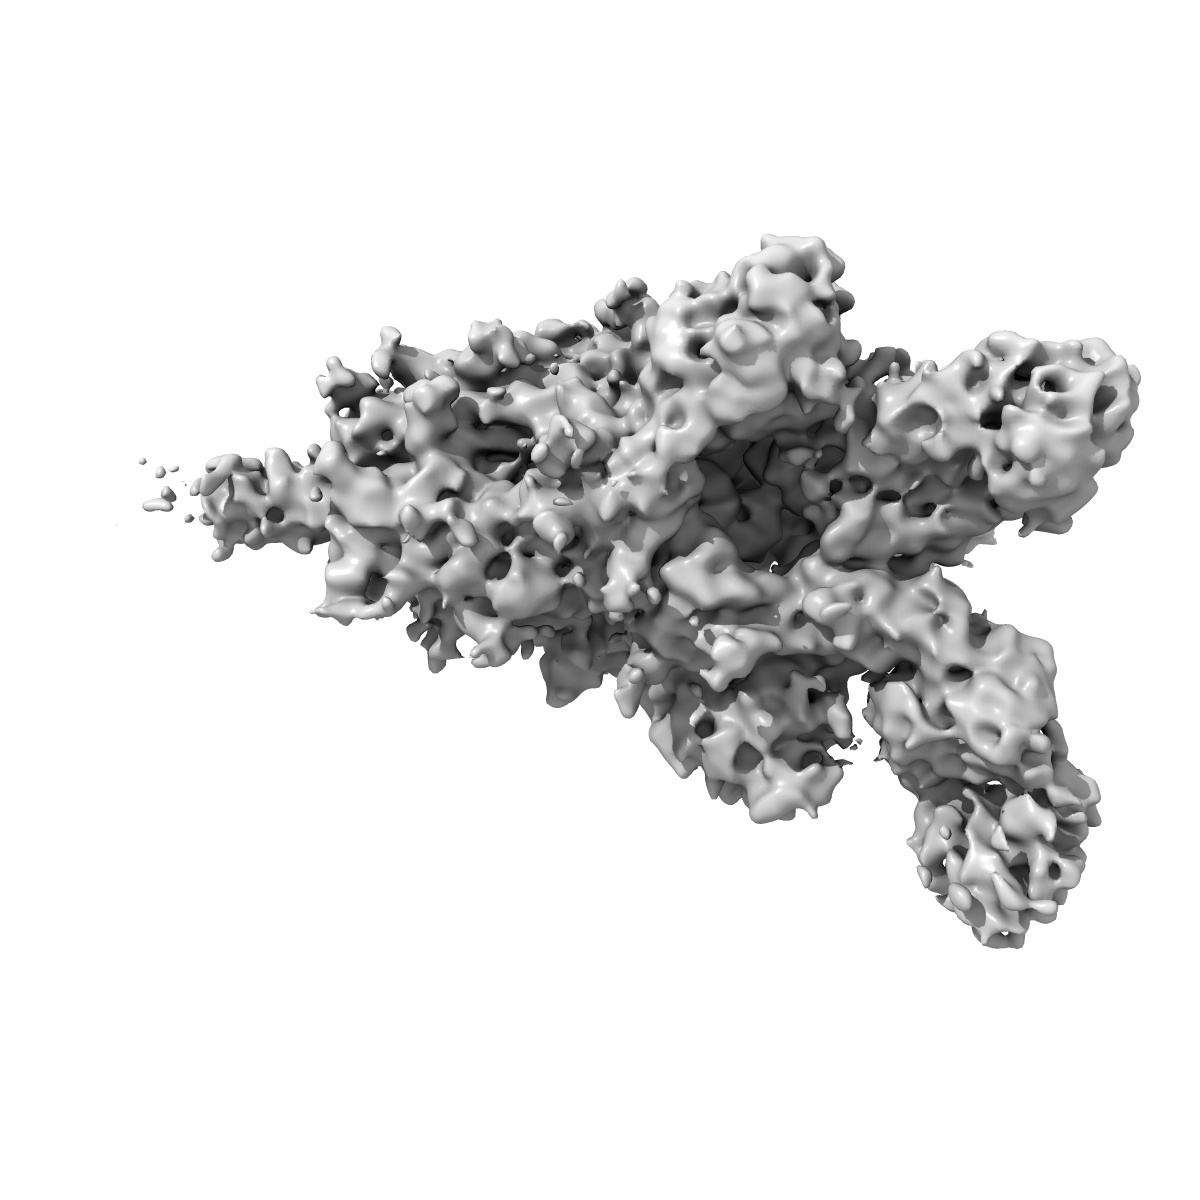

EMD-24607

SARS-CoV-2 spike in complex with the S2X58 neutralizing antibody Fab fragment (two receptor-binding domains open)

Single-particle5.3 Å

Sample: SARS-CoV-2 spike in complex with the S2X58 neutralizing antibody Fab fragment (two receptor-binding domains open)